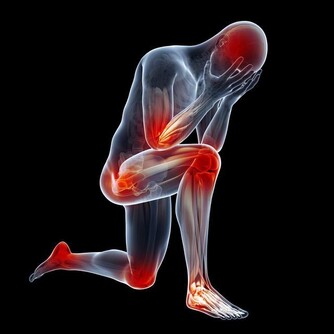

肛門失禁、下腹及腰骶部持續疼痛是直腸癌侵及骶神經叢所致。